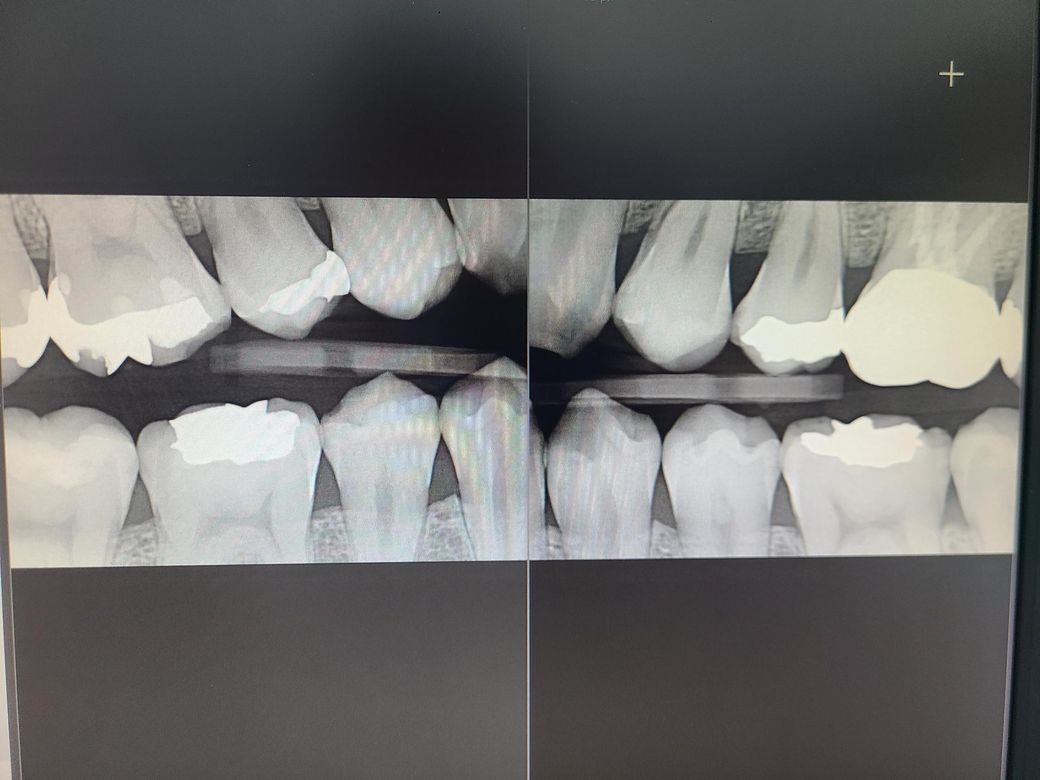

교익 촬영 했는데 한번만 봐주시면 감사드리겠습니다

총 9군데에 인접면 충치가 있다고 진단 받았고

실제 정말 다 수술을 받아야되는건지 한번만 봐주시면 감사드리겠습니다

• 2번 째 사진

엑스레이 상으로 치아 사이에 충치가 있어 보이긴 하지만, 관리를 하면서 지켜볼수도 잇을것같습니다.

3. 엑스레이에서 일부 인접면 충치가 관찰되긴 합니다